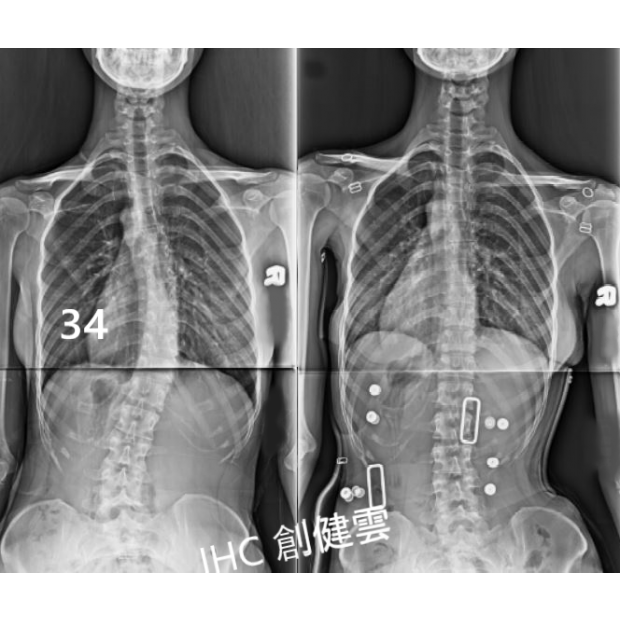

22歲脊椎側彎女孩

胸腰彎34度